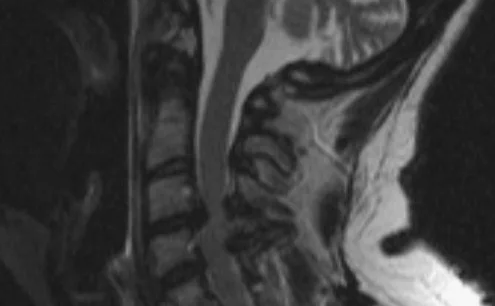

Магнитно-резонансная томография (МРТ):один из самых эффективных методов диагностики заболеваний